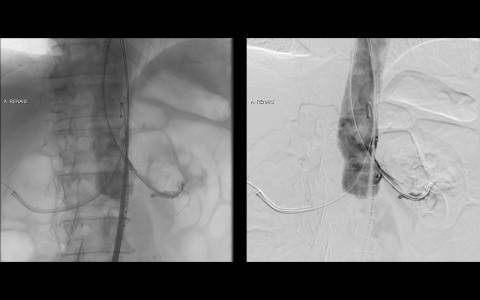

A avaliação por tomografia computadorizada evidenciou um aneurisma infra-renal de colo hostil e acessos vasculares com muita ateromatose. Diante do contexto clínico e de imagem foi optado pelo tratamento endovascular com endoprótese de baixo perfil Incraft CORDIS e técnica de Snorkel Grafts com stents Palmaz CORDIS para as artérias renais.